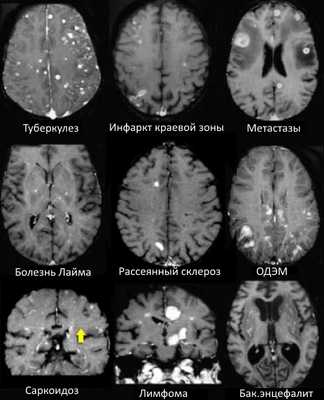

На МР-томограммах продемонстрированы множественные патологические зоны, накапливающие контрастное веществ (некоторые из них описаны далее подробнее).

- Большинство васкулитов характеризуются возникновением точечных очаговых изменений, усиливающихся при контрастировании. Поражение сосудов головного мозга наблюдается при системной красной волчанке, паранеопластическом лимбическом энцефалите, б. Бехчета, сифилисе, гранулематозе Вегенера, б. Шегрена, а также при первичных ангиитах ЦНС.

- Характеризуются выраженным перифокальным отеком.

- Периферические инфаркты краевой зоны могут усиливаться при контрастировании на ранней стадии.